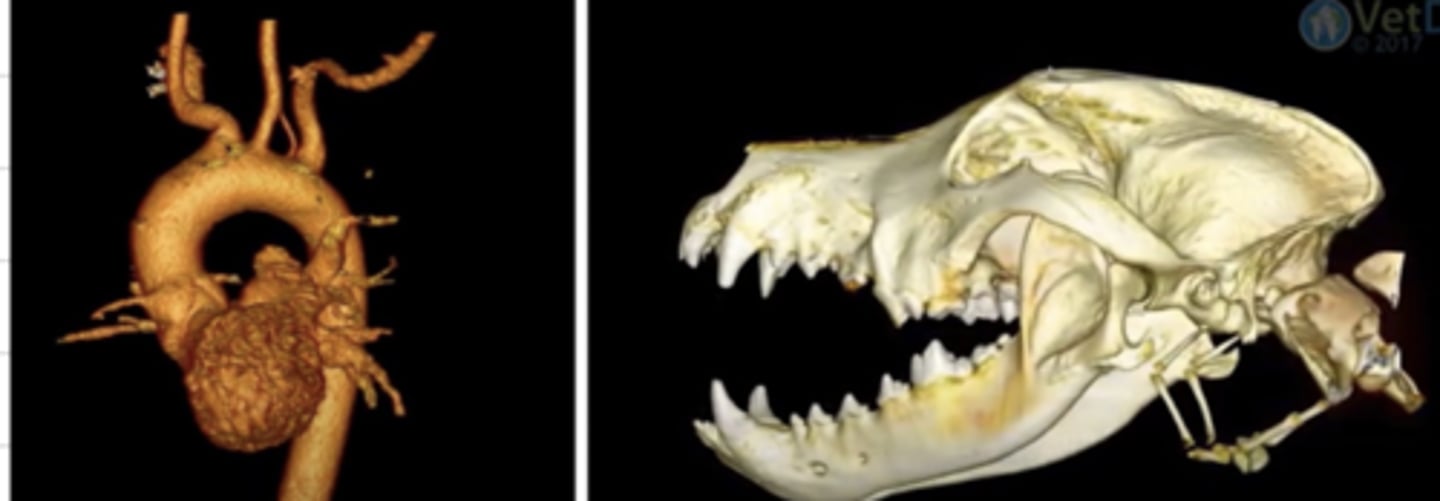

computed tomography (CT)

what diagnostic imaging technique was used to create these images?

computed tomography (CT)

what diagnostic imaging technique was used to create this image?

computed tomography (CT)

what diagnostic imaging technique was used to create these images?

computed tomography (CT)

what diagnostic imaging technique was used to create this image?